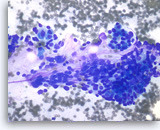

Plasma Cell Neoplasm

Plasma cell neoplasm,

Pancreas FNA, Direct Smear.

The aspirates show dispersed single cells with a prominent plasmacytoid appearance. The tumor cells vary slightly in size. Rare mitoses are seen.

20X

Plasma cell neoplasm,

Pancreas FNA, Direct Smear.

The aspirates show dispersed single cells with a prominent plasmacytoid appearance. The tumor cells vary slightly in size. Rare mitoses are seen.

20X

Plasma cell neoplasm,

Pancreas FNA, Direct Smear.

The tumor cells show perinuclear hof (clearing). Binucleated tumor cells are occasionally seen. Scattered lymphoglandular bodies are seen in the background.

40X

Plasma cell neoplasm,

Pancreas FNA, Direct Smear.

The tumor cells show perinuclear hof (clearing). Binucleated tumor cells are occasionally seen. Scattered lymphoglandular bodies are seen in the background.

40X

Plasma cell neoplasm,

Pancreas FNA, Direct Smear.

The tumor cells have eccentrically located round nuclei with clumped chromatin and small nucleoli.

40X

Plasma cell neoplasm,

Pancreas FNA, Direct Smear.

The tumor cells have eccentrically located round nuclei with clumped chromatin and small nucleoli.

40X

Plasma cell neoplasm,

Pancreas FNA, Cell Block.

Single tumor cells show eccentric nuclei and occasional binucleation. Flow cytometry demonstrate CD38 positive B-cells without surface immunoglobulin expression. The cytomorphologic features along with flow cytometry results are consistent with plasma cell neoplasm. CD138 immunostain can be performed on the cell block section to support the diagnosis if needed.

40X

Plasma cell neoplasm,

Pancreas FNA, Cell Block.

Single tumor cells show eccentric nuclei and occasional binucleation. Flow cytometry demonstrate CD38 positive B-cells without surface immunoglobulin expression. The cytomorphologic features along with flow cytometry results are consistent with plasma cell neoplasm. CD138 immunostain can be performed on the cell block section to support the diagnosis if needed.

40X